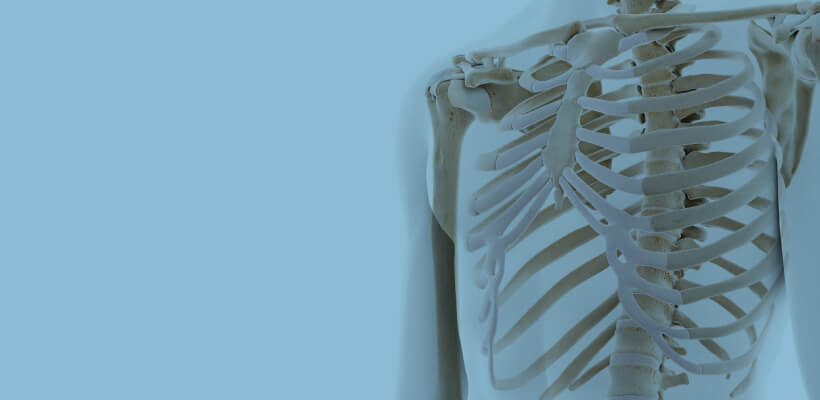

Preoperative simulation

Sternum

A full-scale model of the patient, such as a sternum fixation surgery, can be used for preoperative verification.